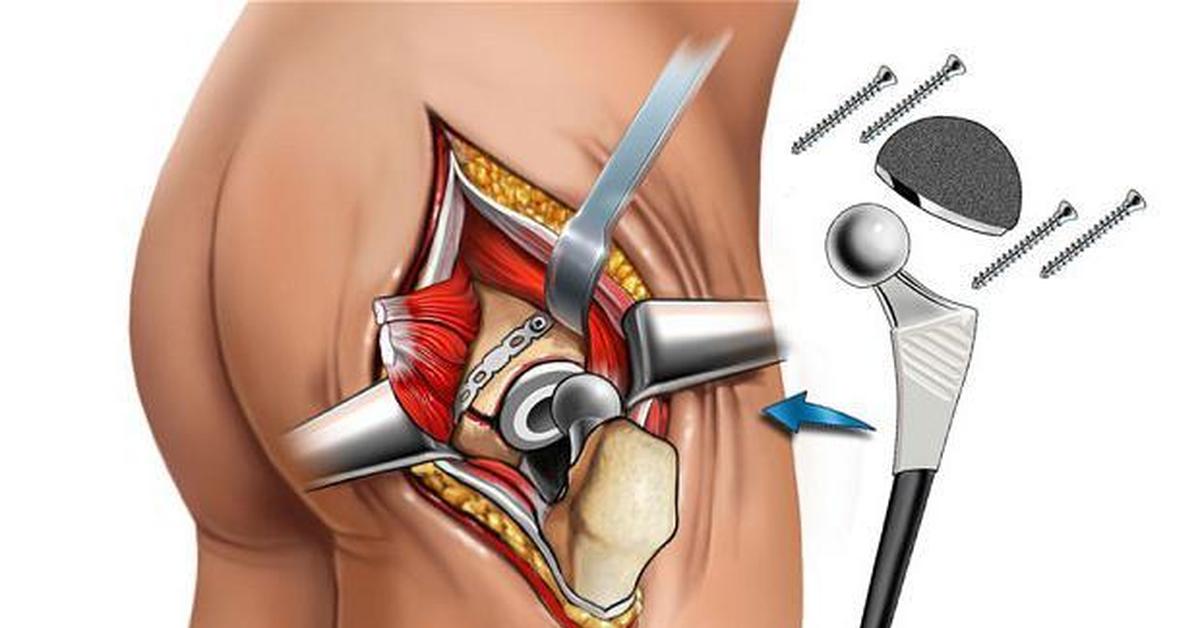

Фотографии и схемы: Коксит правого тазобедренного сустава